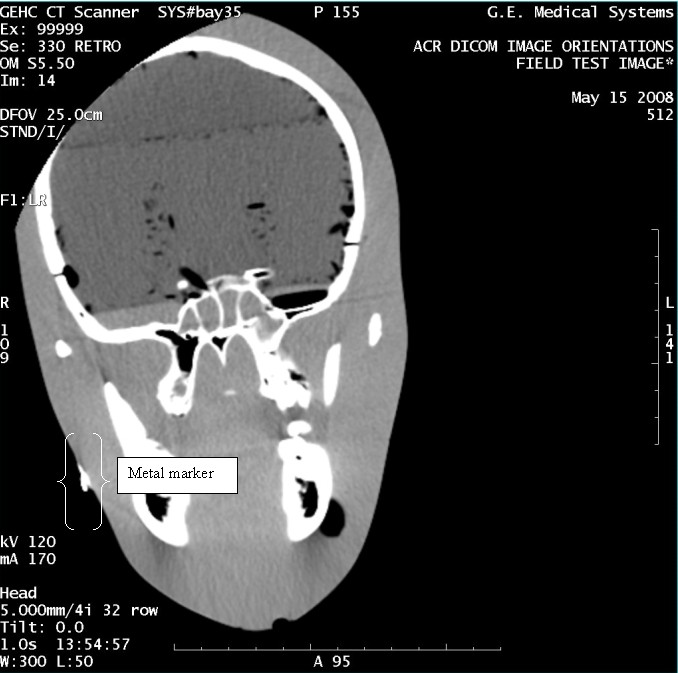

- With the support of the site personnel, examine the images sent

to the Review Station (i.e., 12 series, each with 1 image) and compare

their orientation to the images in this document.

- Each image contains a metal marker on the phantom's right cheek.

- Each image in this document contains a description of the expected

orientation of the metal marker (i.e. to prove Left and Right) as

well as the Posterior and Anterior orientation description.note:

The sample images included in this document use “R”, “L”, “P”, and “A” for “Right”, “Left”, “Posterior” and “Anterior” orientation. The Hospital Review Station may use a different style of annotation. The style used is not relevant to this procedure.

Figure 8. Exam 99999, Series 330